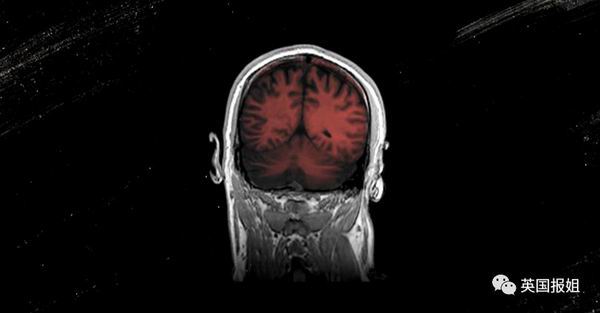

正如.Victory.的经历那样:谵妄的症状并没有在新冠治愈后出现好转。一直到出院两个月后,她仍旧常常会有闻到香烟或木头燃烧的气味的幻觉。为此,她不得不向心理医生寻求帮助。

".人们通常认为,当病人恢复健康并离开医院时,就可以了。但我担心新冠病毒没有要我的命,但是却足以影响我的身体,在我康复后杀死我.…"